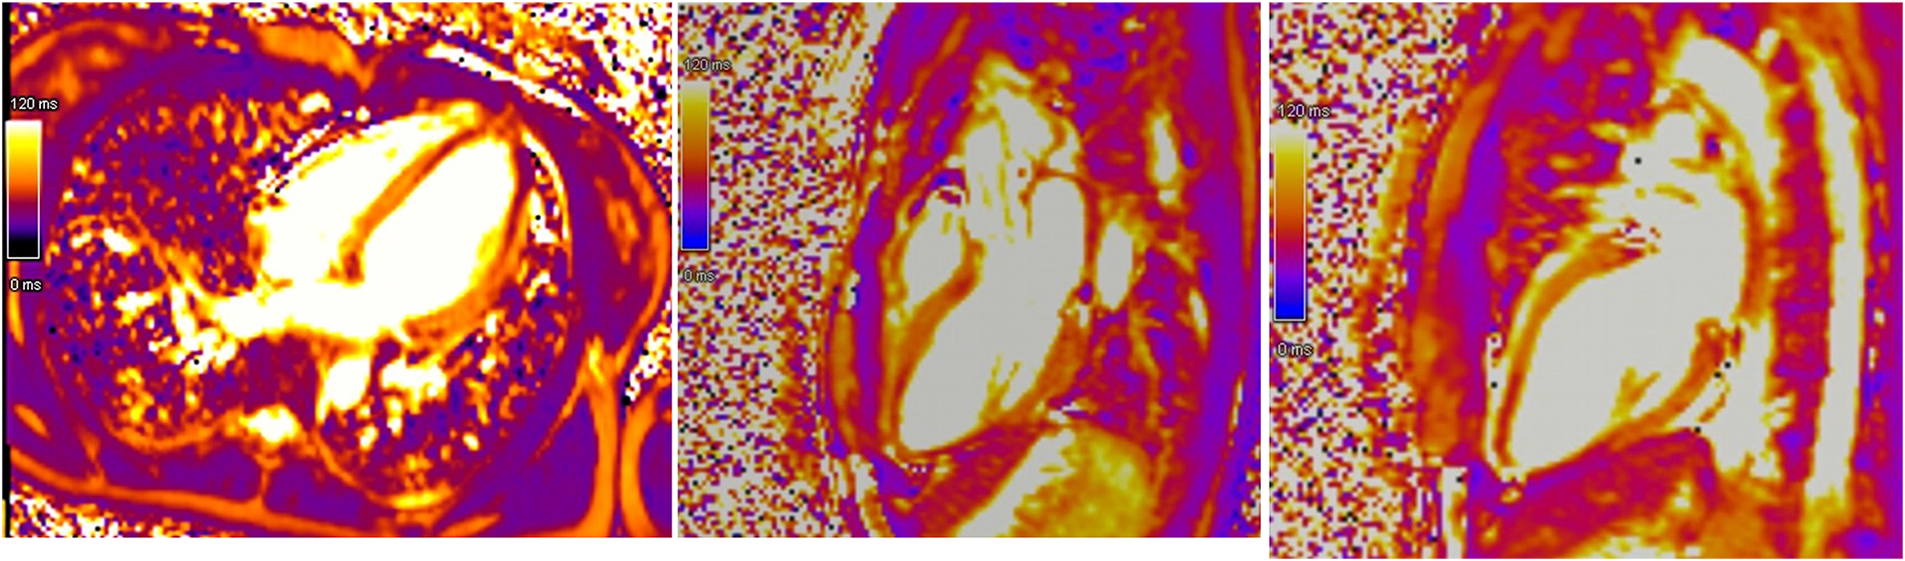

Initial evaluation with TTE was suggestive of cardiogenic shock with an estimated LVEF of 15 to 20%. Because of the severity of the situation and the young age of the patient, a transfer to the academic tertiary care hospital was decided. Upon arrival, a total-body-CT was performed to rule out intracranial bleeding, pulmonary embolism, and an infectious or neoplastic process. TTE was repeated on day one and was relevant for severe LV dysfunction (LVEF of 24%), and findings suggestive of reverse TTS, with basal and mid-ventricular segments akinesia and a spared apical contractility (Figure 3: Transthoracic echocardiography performed at day one, showing a severely reduced left ventricular ejection fraction (24%) with basal and midventricular segments akinesia, and preserved apical contraction. There was no significant valvulopathy and right ventricular function was normal. Panel A: Diastole, Panel B: Systole). In the absence of localized wall motion abnormalities matching the territory of a coronary artery, and considering the young age of the patient, with no known personal or familial cardiovascular risk factors, coronary angiography was not performed as the probability of coronary artery disease was considered very low. Hs troponin T levels rose to a peak of 1,894 ng/L on day one, with a subsequent decrease. The clinical situation rapidly improved and the patient was extubated on day two. On day four, a cardiac MRI was performed, showing an improvement of the LVEF to 46%. Horizontal long-axis, color-coded images from T2-mapping revealed hyperintensity in the basal and mid-ventricular segments of the left ventricle that confirmed the presence of regional circumferential myocardial oedema (Figure 4: cardiac MRI images from T2-mapping revealing myocardial oedema in four, three and two-chamber views), as well as the absence of late gadolinium enhancement (supporting the idea that there was no irreversible myocardial injury) (16). Based on these observations, two diagnostic hypotheses were put forward: reverse TTS or an inflammatory cardiomyopathy. However, regarding the latter hypothesis, the Lake Louise criteria were not fulfilled (17), reason why reverse TTS was considered the most likely diagnosis, despite the patient having an InterTak Diagnostic Score of only 46 (25 points for female gender, 12 points for no ST-segment depression and 9 points for the acute neurological trigger), meaning a 9.8% probability of TTS (1).

Figure 4

Cardiac MRI images from T2-mapping revealing myocardial oedema in four, three and two-chamber views.